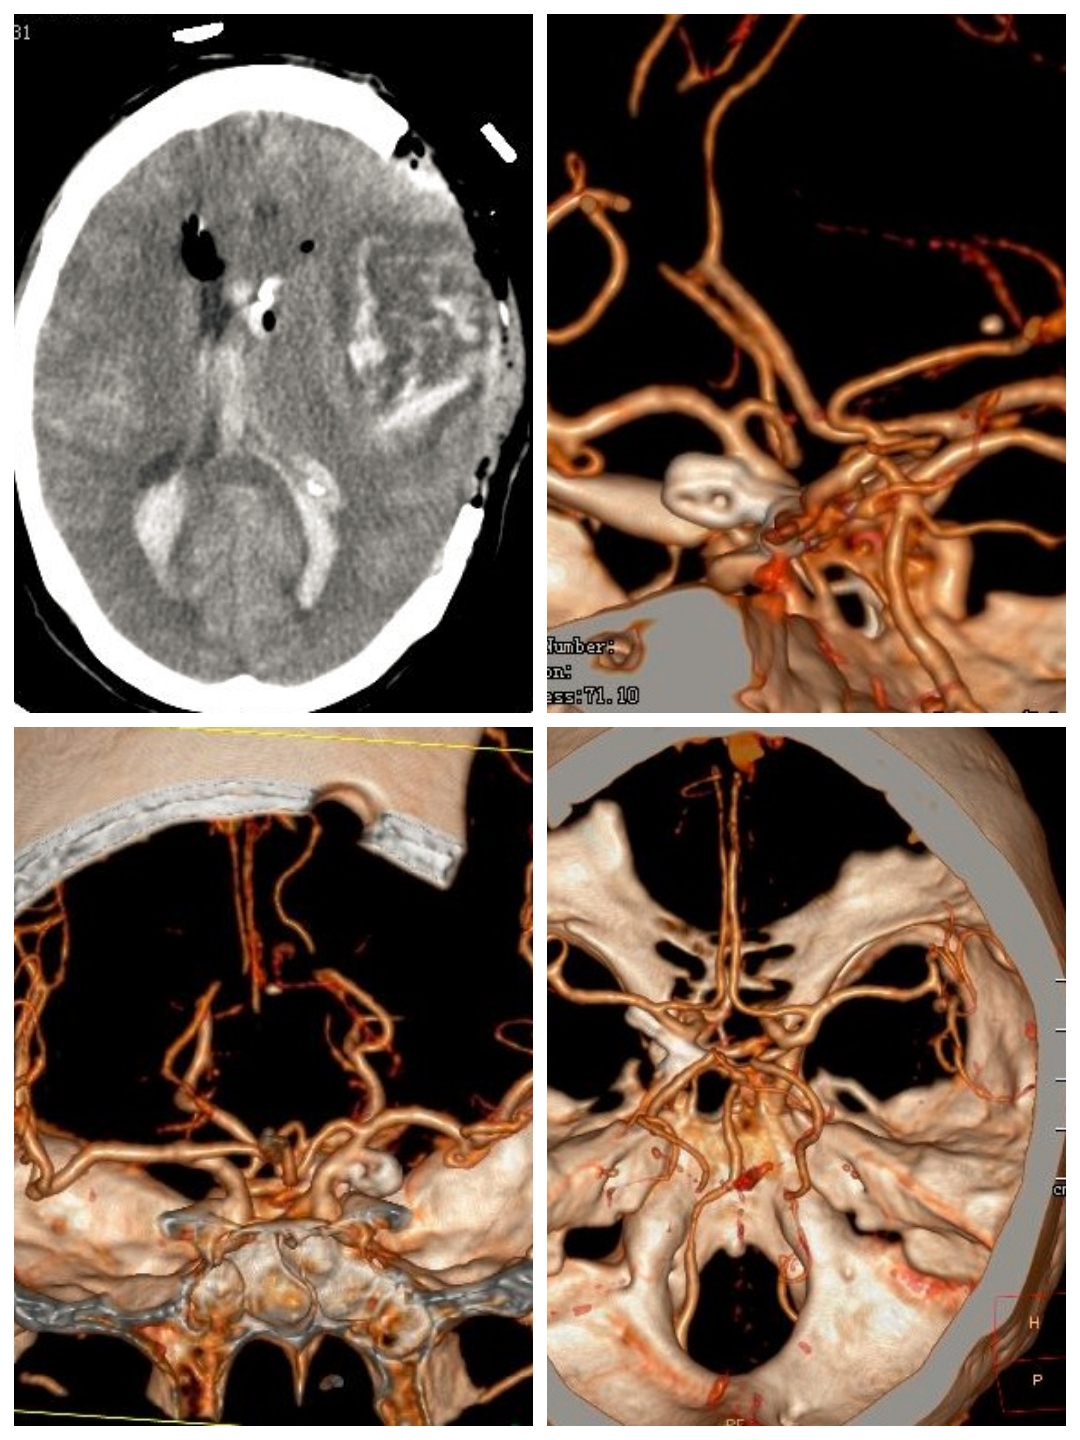

刘某,女性,69岁,因“视物模糊伴头晕不适一个月”入院。

MRI提示左枕叶脑梗塞,粗看MRA还可以,左侧血管较右侧血管稍稀疏纤细一点。

进一步DSA检查提示左侧颈内动脉末端狭窄~果然比MRA精准

予以双导丝双球囊扩张,稀疏的颅内血管终于开枝散叶。术后患者症状改善,治疗效果非常满意。